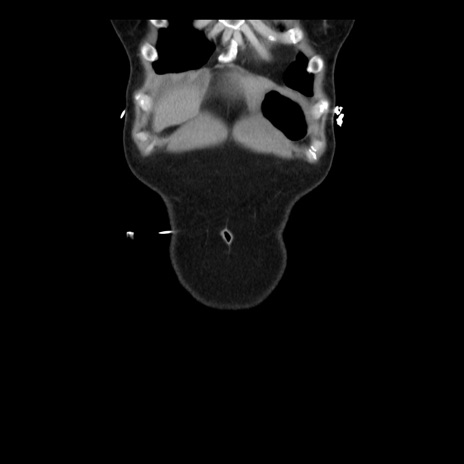

矢状断像